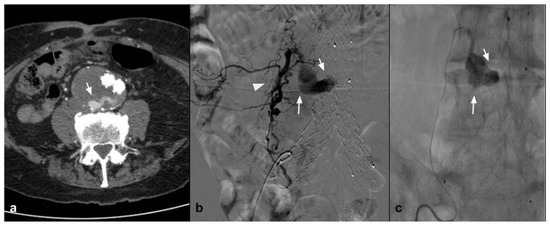

One condition that has been treated with NALEA is splenic aneurysm. A number of papers have recently been published demonstrating the possibility of embolization using NALEA in combination with coils. Both proximal and peripheral splenic aneurysms with different anatomical conformation have been treated in the literature [17,20] (Figure 4).

Figure 4.

(a) Coronal CTA MIP demonstrates post surgical pseudoaneurysm of left gastric artery (white arrows). (b) DSA performed with Simmons 1 catheter at the level of the ostium of the celiac trunk confirms the presence of the pseudoaneurysm (white arrow). (c) DSA performed with microcatheter in the left gastric artery highlights a saccular dilation (white arrow) of the left gastric artery with regular patency of the efferent vessel (black arrow). (d) Post-procedure DSA control demonstrates complete exclusion of the treated PSA (asterisk) with an Onyx 18 cast completely occupying the malacic vessel performing an “endovascular ligature technique” (white arrow).

A second solid experience was published by Urbano et al. in 2017 [65], who performed in 22 consecutive patients and 25 lesions for symptomatic AMLs or AMLs > 4 cm. Mean AML size in this study was 7 cm. In this study, the peculiarity is that EVOH copolymer was the only embolic agent used. A postembolization syndrome was scheduled in 18.5% of patients, maybe because, when using only Onyx, a large quantity of EVOH was injected. Also for Urbano et al., AML embolization with EVOH copolymer is feasible, safe, and effective (Figure 5).

Figure 5.

(a) Coronal CTA MIP highlights a large angiomyolipoma of the right kidney lower third (white arrow). (b) DSA performed with a direct injection in the right renal artery confirms the lesion with an abnormal arterial vascularization (black arrows). (c) A post procedure DSA check demonstrates the presence of the Squid 34 cast which completely occludes the tributary arteries of the lesion (white arrows) and preservation of the healthy renal parenchyma (black arrows).